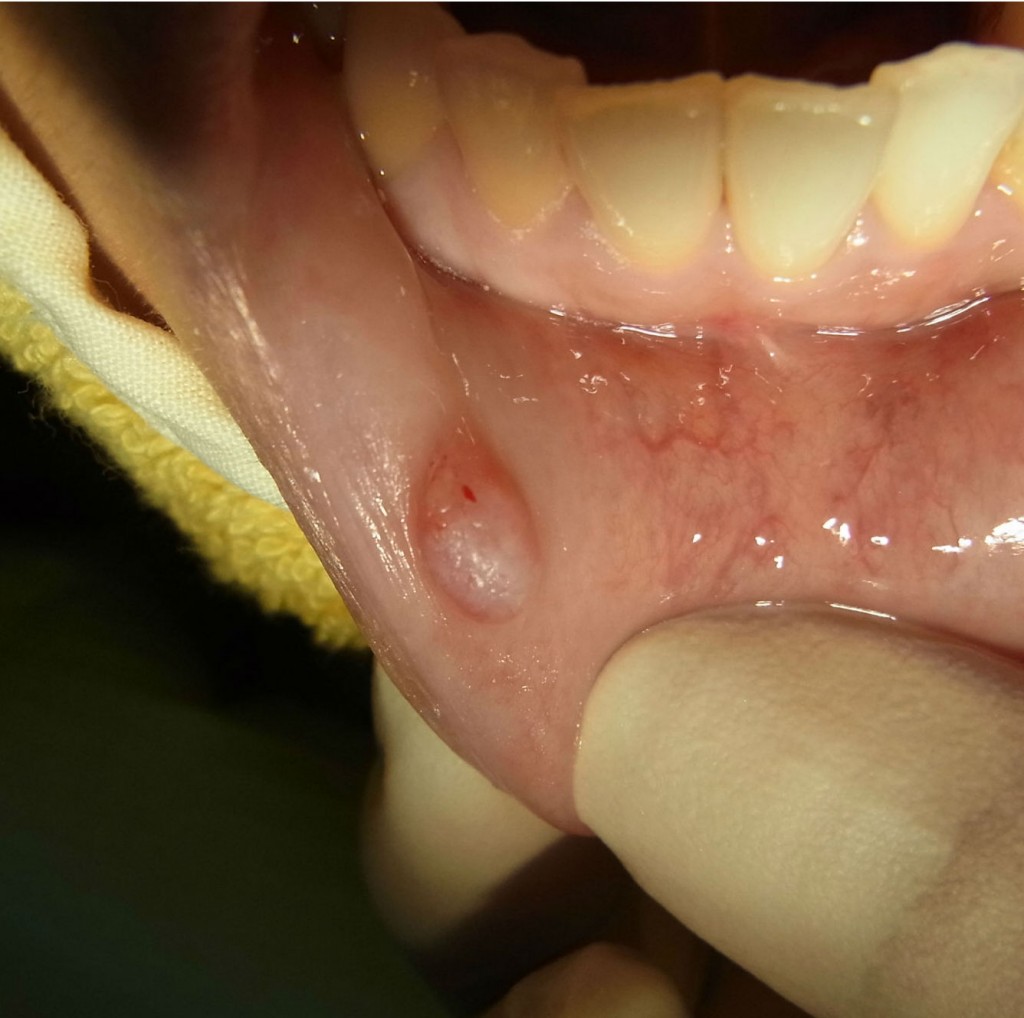

心配していた台風が、この地を去り、徐々に日差しが出てきました。 さて、以前口内炎のレーザー処置についてお話ししました。 口内炎は、とても気になる不快なものですが、お口の中で発生する様々な症状のひとつに粘液嚢胞というものがあります。 舌や舌の下(口腔底)、ほほの内側にできることもありますが、一番よく発生するのは下口唇です。 粘液嚢胞は唾液腺が出口をふさがれて、唾液がたまった状態で、特に痛みもなく小豆大ほどのふくらみになります。 自然に治ることもありますが、再発を繰り返すことが多いとも言われています。 粘液嚢胞 まず抜歯と同様に麻酔をします。そしてメスを使って摘出し、縫合して終了です。 とりました 1週間後に抜糸しました。 終了 発見し除去する際は、つぶさないようにして来院ください。